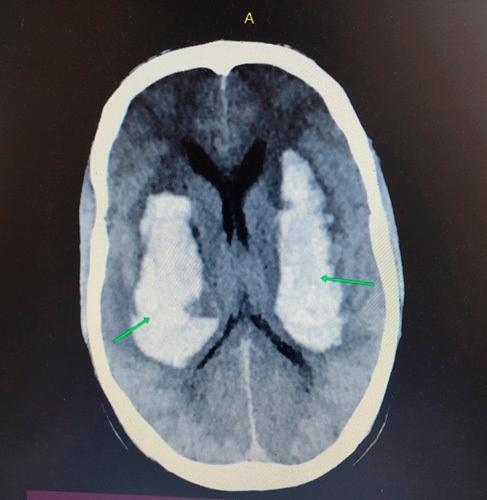

Twenty-three-year-old male with no prior comorbidities presented to emergency with sudden onset loss of consciousness and 1 episode of seizure. No history of intoxication or trauma was given. Glasgow Coma Scale at presentation was E1V2M2. CT scan head revealed bilateral basal ganglia haematoma along intraventricular haemorrhage.

一名23岁无既往合并症的男性因突发意识丧失和1次癫痫发作就诊于急诊科。无中毒或外伤史。就诊时格拉斯哥昏迷量表评分为E1V2M2。头颅CT扫描显示双侧基底节血肿伴脑室内出血。